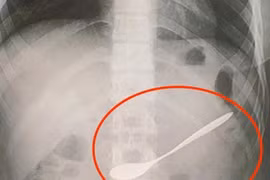

Chiều 15-3, PGS.TS.BS Trần Minh Trường, Phó Giám đốc Bệnh viện Chợ Rẫy cho biết, đơn vị này vừa thực hiện thành công gắp dị vật đường thở rất khó thực hiện bởi trong quá trình thực hiện nội soi bệnh nhân đã ngưng thở 4 lần, tụt huyết áp.